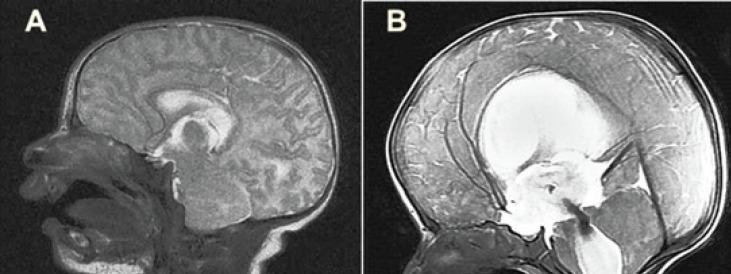

MATERIALS & METHODS: A total of 84 cases in 2 groups between 0 and 3 months, followed-up at Firat Universitesi Hastanesi, Beyin Cerrahisi Klinigi, Elazig, Turkiye due to in 2010-2013, were enrolled. Two groups were created for the study. Group 1; patients with HCP and Group 2; as control group without HCP. In both groups, the length of the A2 segment of ACA was measured from its origin to the junction of the genu and body portions of the corpus callosum on T2 mid-sagittal magnetic resonance (MR) scans. For all cases, axial MR imaging scans were used to calculate Evans' index (EI), and the cases were divided into three groups: Group A, EI ≥50%; Group B, EI of 40-50% and Group C, EI <40%. The two groups (Groups 1 and 2) were compared with respect to ACA length, and the correlation with the EI was quantified. P values below 0.05 were considered statistically significant.

Mean length of ACA was 57.3 mm in Group 1 and 37.5 mm in Group 2. EI increased as the length of ACA increased. A statistical comparison of the two groups revealed that the ACA length was significantly greater in Group 1. The relationship between EI and ACA length was statistically significant.